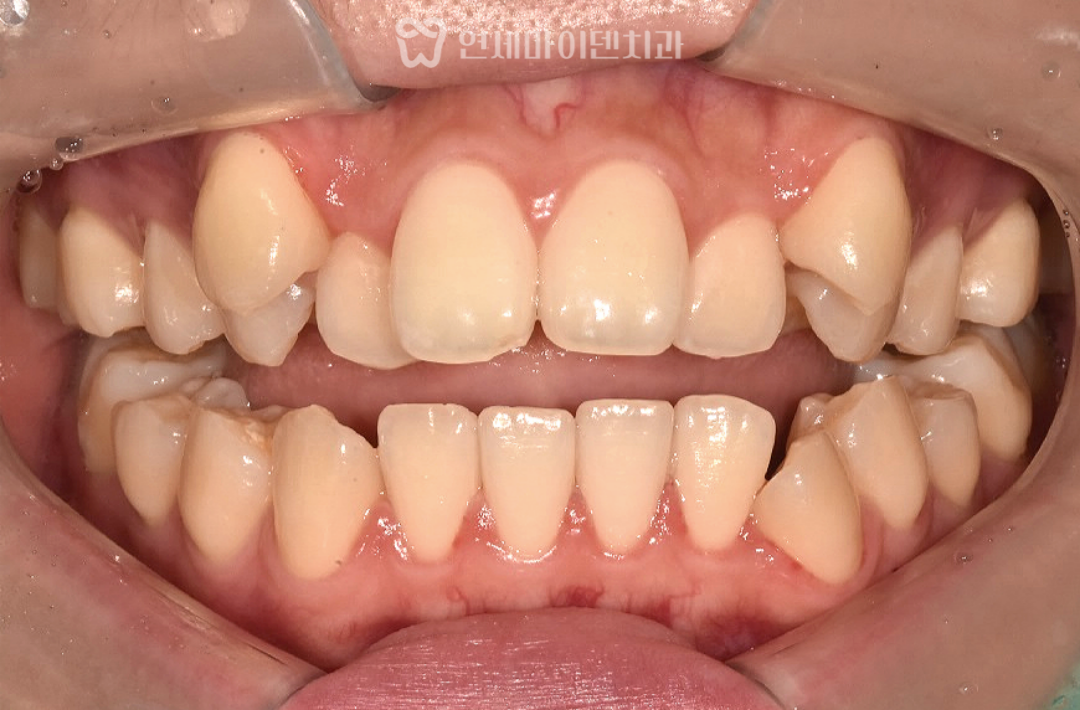

치료 완료 및 결과 분석

약 23개월의 교정 치료 후,

앞니 개방교합은 완전히 닫혔고

치아 배열도 가지런하게 정리되었습니다.

좌우 중심선이 맞춰졌고,

어금니 교합 역시 고르게 맞물리도록 조정되었습니다.

전체 치열은 안정적인 U자형으로 형성되었습니다.